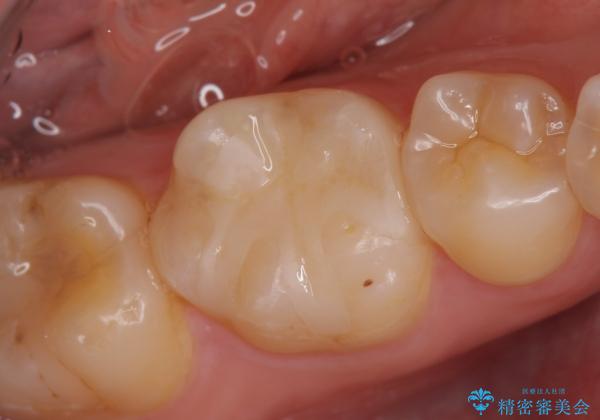

- 右下の銀歯が気になるといらっしゃった方の症例です。

右下6番目の銀歯を除去後、セラミックインレーによる修復を行いました。

当院のセラミックインレーはemaxという強度と審美性に優れた材料を使用しています。

またプレス方式でインレーを製作しているため、削り出しで製作するCADCAMより優れた適合性も持ち合わせており、虫歯が再発しにくい修復物です。